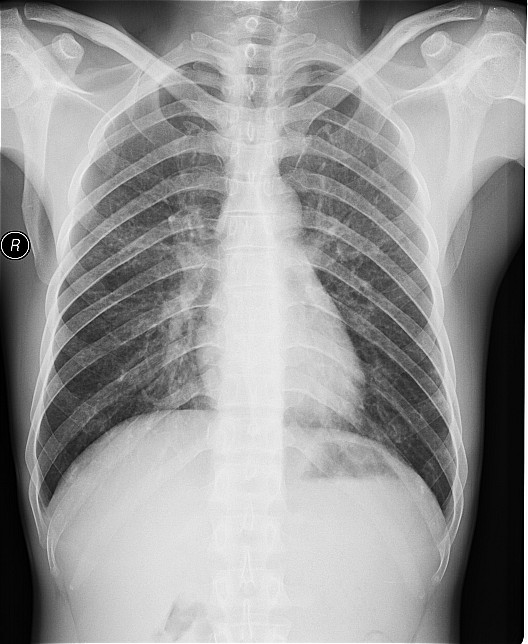

一钨矿工厂因有毒气体泄漏(据说是硝酸)造成十多名工人中毒,均出现不同程度的咳嗽,气逼,心跳加快等中毒症状.其中有几例患者胸片出现小点片状,结节状阴影.是此次中毒引起的肺部改变还是原来就患有矽肺病或其它病变.

肺水肿,及原来就患有矽肺病

原就有的矽肺,未见中毒性肺水肿

矽肺,部分胸片可见肺水肿。治疗复查